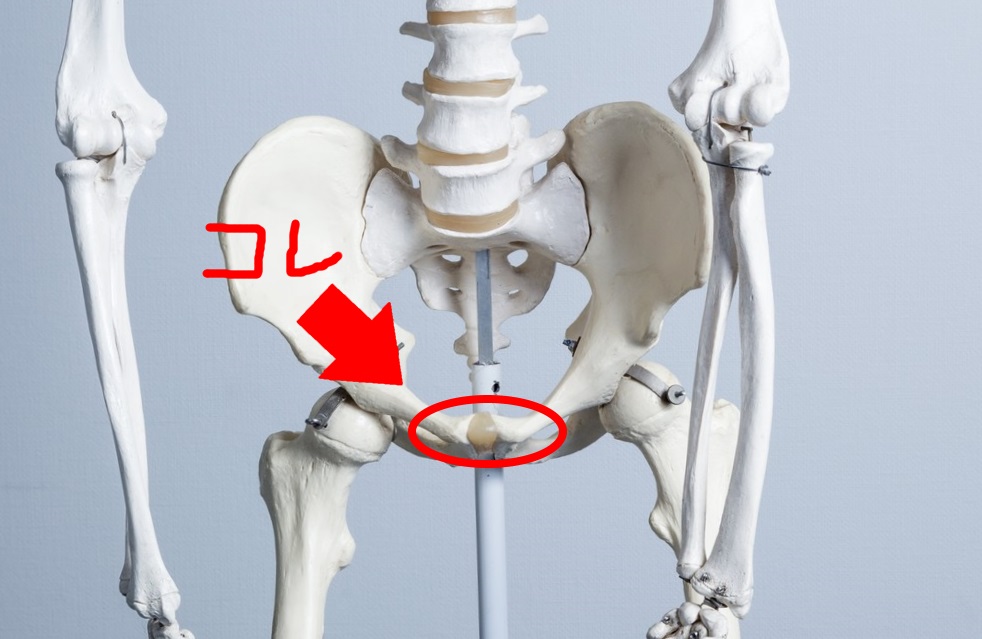

続いて恥骨を探します。

DFreeは恥骨の上1cm位の場所に超音波センサーを取り付けて、ぼう胱の中の尿の溜まり具合を測定します。

そのため、毎回正しい位置にセンサーを取り付けることが重要なわけです。

・・・恥骨・・・??(手で探ってみて)・・・これ??

N田さん、恥骨の位置がよくわかりません!

上の写真をイメージして探してみましょう!固くなっている場所が恥骨です。慣れればすぐわかるようになります!

わかりました。多分この辺りかな…!?

ぼう胱は、恥骨から上1cmのところにあるので、センサーを装着してみましょう!